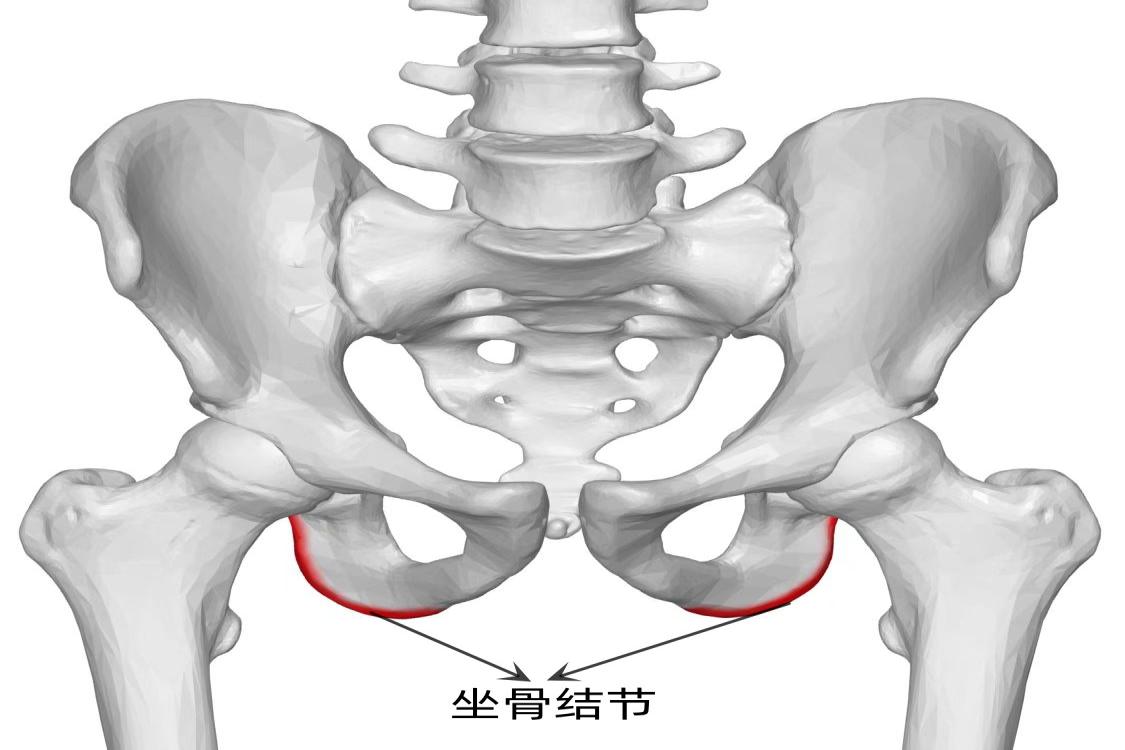

坐骨结节的位置示意图

坐骨结节的位置在人体臀部的最底部,坐骨的一部分就有坐骨结节,人体呈坐姿时,坐骨结节正好与板凳表面相接触。

1、坐骨结节的位置在人体臀部的最底部。臀部主要构成是骨盆,坐骨是骨盆的主要结构,坐骨可以分成上下两支,两支骨交接处有粗隆向后下突出就是坐骨结节。

2、人体呈坐姿时,坐骨结节正好与板凳表面相接触,也就是接触凳子的左右两块臀部的骨头。